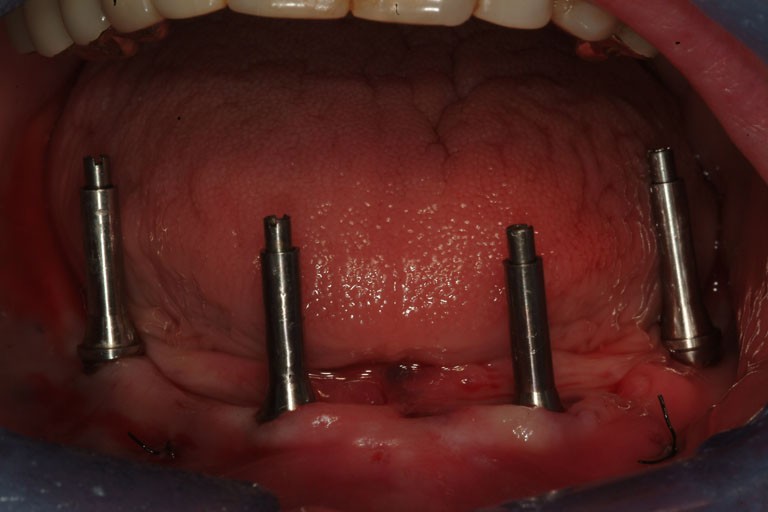

Carico immediato con dima chirugica digitale